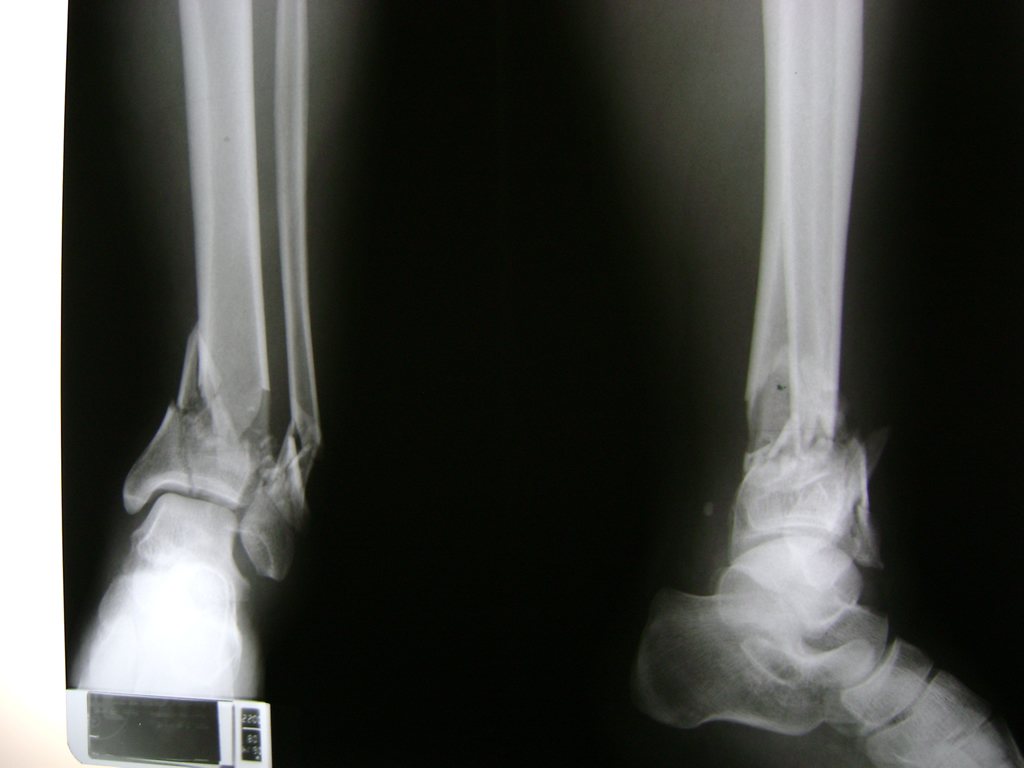

Una fractura de tobillo es la rotura de uno o más de los huesos del tobillo. Estas fracturas pueden ser:

- Completas (el hueso está perforado y está en 2 partes).

- Producirse en uno o ambos lados del tobillo.

- Los extremos de los huesos están desalineados entre sí (desplazados).

- La fractura se extiende hasta la articulación del tobillo (fractura intra-articular).